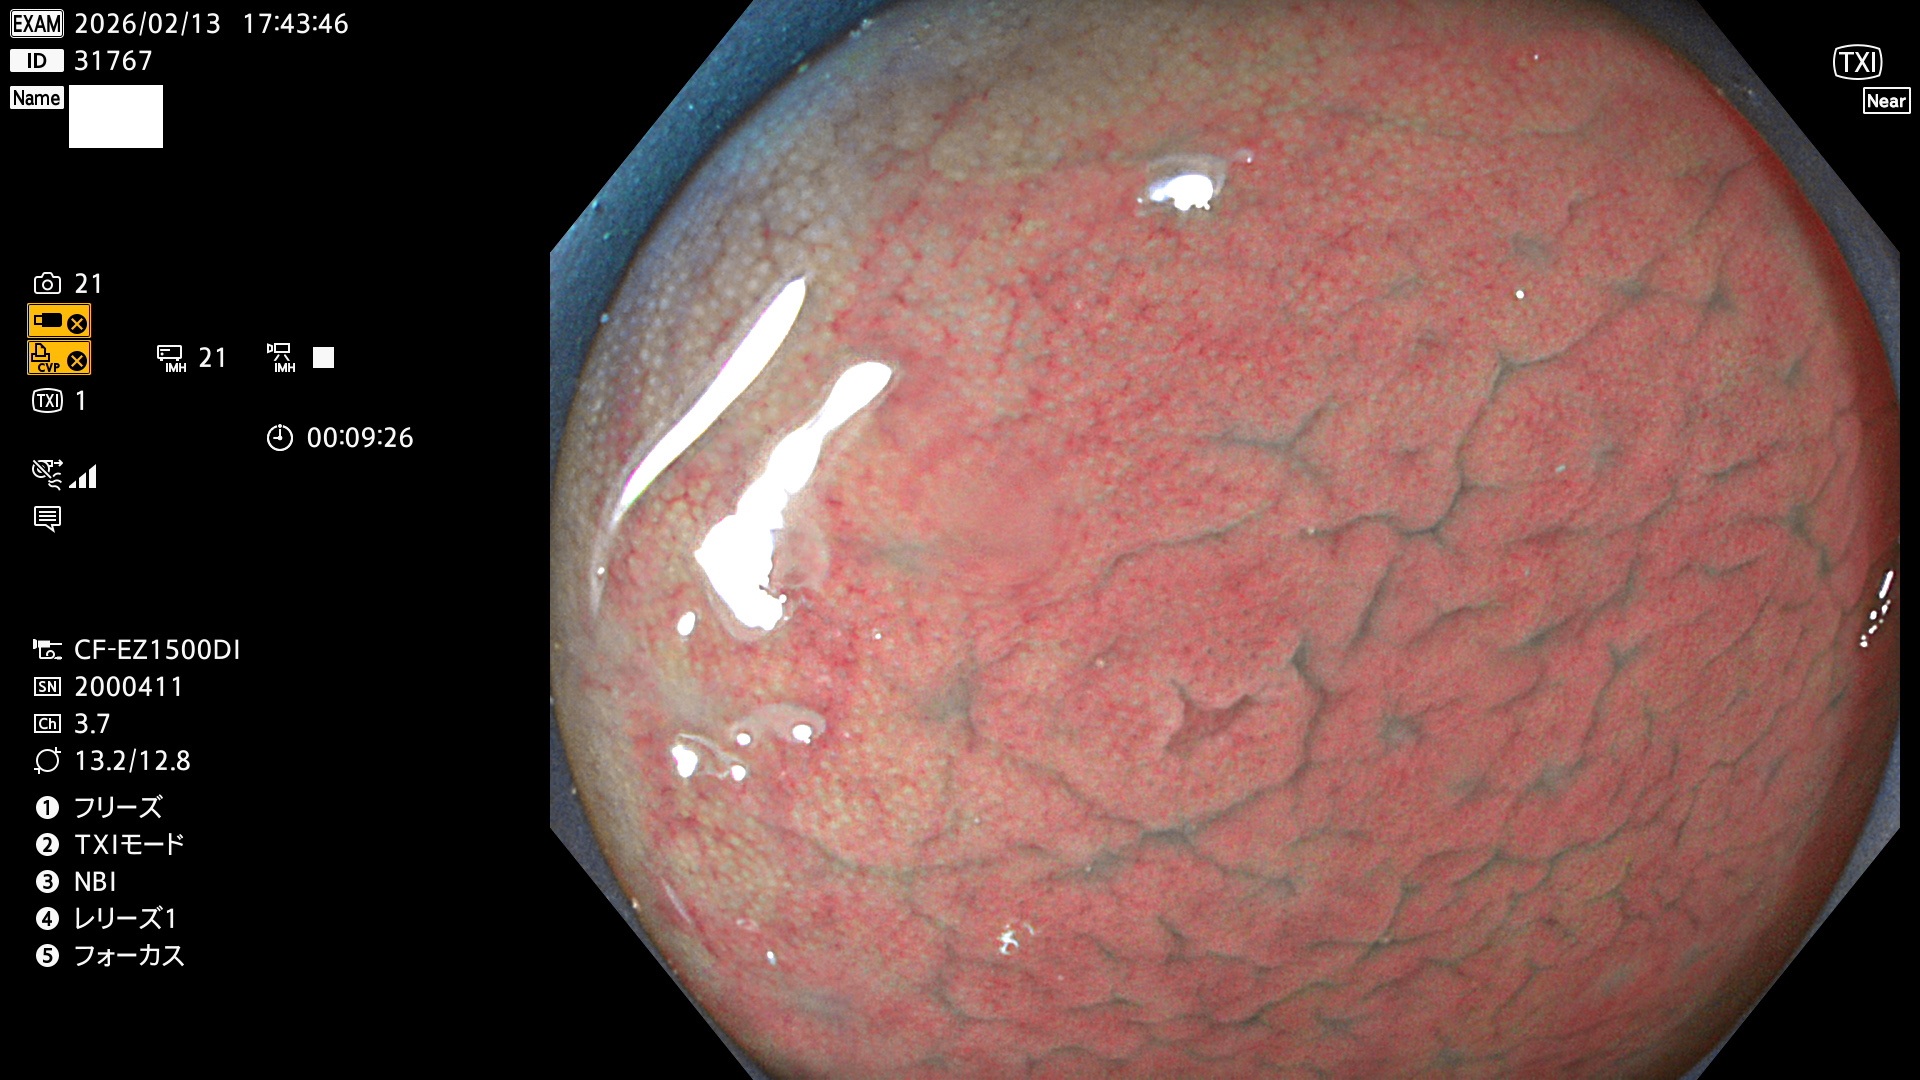

毎週の検査(木・金・土・日)に発見されたUbとUc型・腺腫を、その週の日曜の夜にUPし1週間、提示します。

2026年2月12日〜2月15日の4日間(40件)5個 (Uc_ADR=5個/40人=13%)